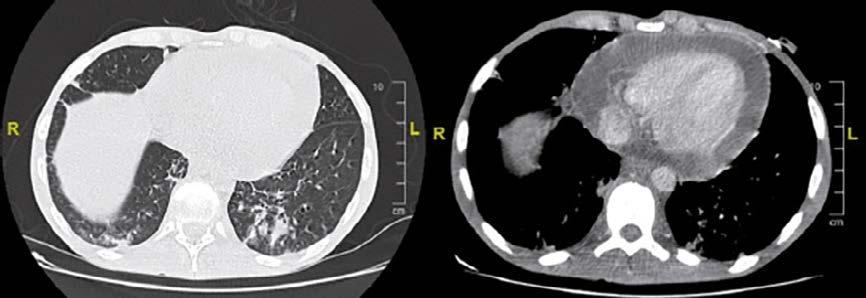

Los hallazgos de nuestro estudio, parecen indicar que hay un beneficio directo en la reducción de las hospitalizaciones por neumonía en pacientes bajo 5 años que fueron inmunizados con PCV13 vs PCV10. No obstante, las mayores limitaciones de nuestro estudio son el tipo de diseño retrospectivo al igual que la debilidad del diagnóstico clínico y no radiológico de neumonía que podría incluir enferme-